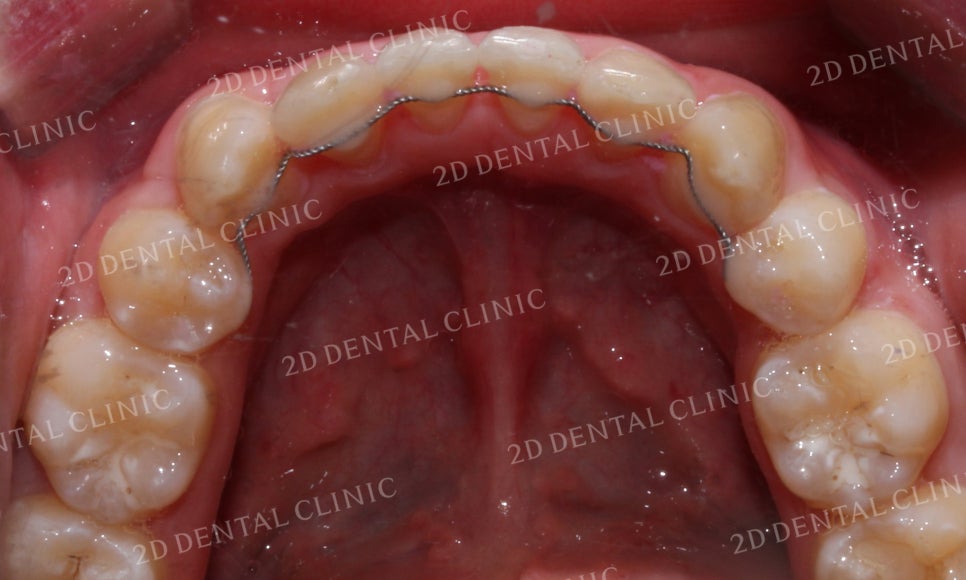

<Before> <After>

하악의 전치부 사진입니다.

좁은 악궁으로 인해 크라우딩이 심했던

교정 전 모습과 달리 교정 후 삐뚤거림이 사라지고

가지런하게 배열된 모습입니다.